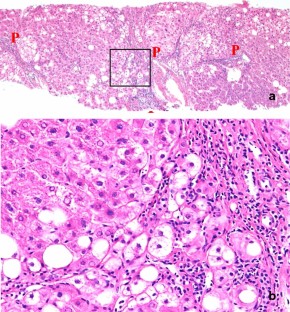

Nonalcoholic fatty liver disease (NAFLD) is based on the concept of pathological morphology as well as clinical findings, and is broadly categorized into nonalcoholic fatty liver (NAFL) and nonalcoholic steatohepatitis (NASH). The differential diagnosis between NAFL and NASH is important because NASH has the potential to progress to cirrhosis and hepatocellular carcinoma. NAFL is simple hepatic steatosis without hepatocellular injury, while NASH is characterized by macrovesicular steatosis, inflammation, and ballooning hepatocytes with a predominantly centrilobular (zone 3) distribution. Liver biopsy is a useful test for diagnosing NAFLD, but it is invasive. Therefore, various noninvasive methods including diagnostic imaging have been developed in recent years. To verify their usefulness, it is necessary to clarify in detail how the pathological findings are reflected in the image findings as imaging and histopathological findings are closely related. We describe the main histological features of NAFLD, i.e., steatosis, inflammation, ballooning hepatocytes, Mallory-Denk bodies, and fibrosis, as well as the evolutional process to liver cirrhosis.

Fig. 4